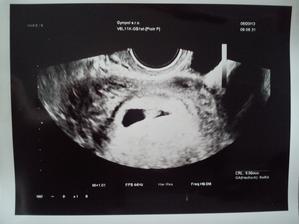

Nasa vytuzena laska

@leonie777 no moja termin mam od 24.12 do 6.1 veru krasny darcek dostaneme )))ak ma to chyti tak dufam ,ze az na stedry den po vecery

@marta2 yes, fakt super termin, bude darcek na sviatky 🙂 kazdopadne mala chilli elin si vyberie, kedy sa jej bude chciet 🙂 ty sa drz zlatino ... opatruj sa, aj drobca 🙂 chalani uz to vedia? velka radost v celej rodinke